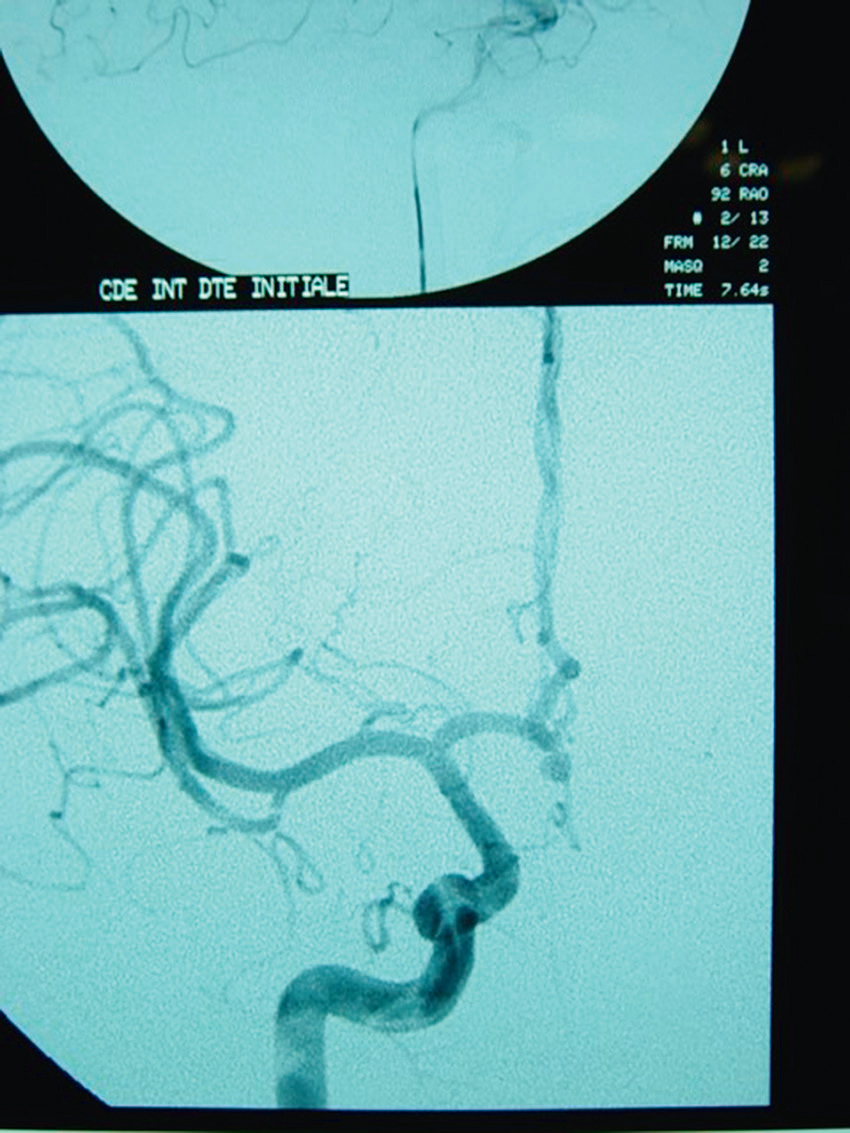

Devant cette atteinte du nerf III avec douleurs associées, vous souhaitez éliminer la présence d’un anévrisme carotidien, raison pour laquelle vous décidez de réaliser une IRM cérébrale avec ARM cervicale. Il n’y a pas d’anévrisme mais d’autres images attirent votre attention. Quelles sont les coupes et séquences utilisées pour ces deux images (fig. 31.12 et 31.13) ?

L'image montre une coupe transversale d'un cerveau humain obtenue par imagerie par résonance magnétique (IRM). Cette image est en niveaux de gris et présente des structures cérébrales distinctes. On peut observer les hémisphères cérébraux, séparés par la fissure interhémisphérique. Les zones plus claires sur l'image représentent des anomalies ou des lésions, qui peuvent être dues à diverses conditions médicales telles que la sclérose en plaques, les tumeurs, ou les accidents vasculaires cérébraux. Les zones sombres au centre de l'image correspondent aux ventricules cérébraux, qui contiennent le liquide céphalorachidien. Cette image est intéressante car elle permet aux professionnels de la santé de diagnostiquer et de surveiller les maladies neurologiques en visualisant les structures internes du cerveau et en identifiant les anomalies. Les détails observables, comme la localisation et la taille des lésions, sont cruciaux pour une évaluation approfondie. Ce type d'imagerie aide à comprendre l'étendue des dommages et à planifier des traitements appropriés. En analysant ces images, les médecins peuvent mieux comprendre la santé cérébrale et prendre des décisions éclairées concernant les soins à apporter au patient.

L'image montre une coupe transversale d'un cerveau humain obtenue par imagerie par résonance magnétique (IRM). Cette image en niveaux de gris présente les structures internes du cerveau, y compris les circonvolutions et les sillons. Les variations de teintes indiquent différentes densités de tissus et de liquides. Les zones plus claires peuvent correspondre à des anomalies ou des lésions, telles que des tumeurs, des plaques ou des signes de maladies neurologiques. Les zones sombres au centre de l'image représentent les ventricules cérébraux, remplis de liquide céphalorachidien. Cette image est utilisée pour diagnostiquer et surveiller diverses pathologies cérébrales, fournissant des informations cruciales pour les professionnels de la santé. L'IRM est une technique non invasive qui permet de visualiser avec précision les détails anatomiques du cerveau sans utiliser de rayonnement ionisant. Grâce à cette image, les médecins peuvent identifier des anomalies, évaluer leur étendue et planifier les traitements nécessaires pour les patients atteints de troubles neurologiques. Les coupes transversales du cerveau montrent également les principales régions cérébrales, permettant une meilleure compréhension de la structure et des fonctions du cerveau humain.

593

-

- A coupes axiales en séquence T2 injectées

- B coupes axiales en séquence T1 non injectées

- C coupes sagittales en séquence T2/FLAIR

- D coupes axiales en séquence T2/FLAIR

- E coupes axiales en séquence 3D TOF